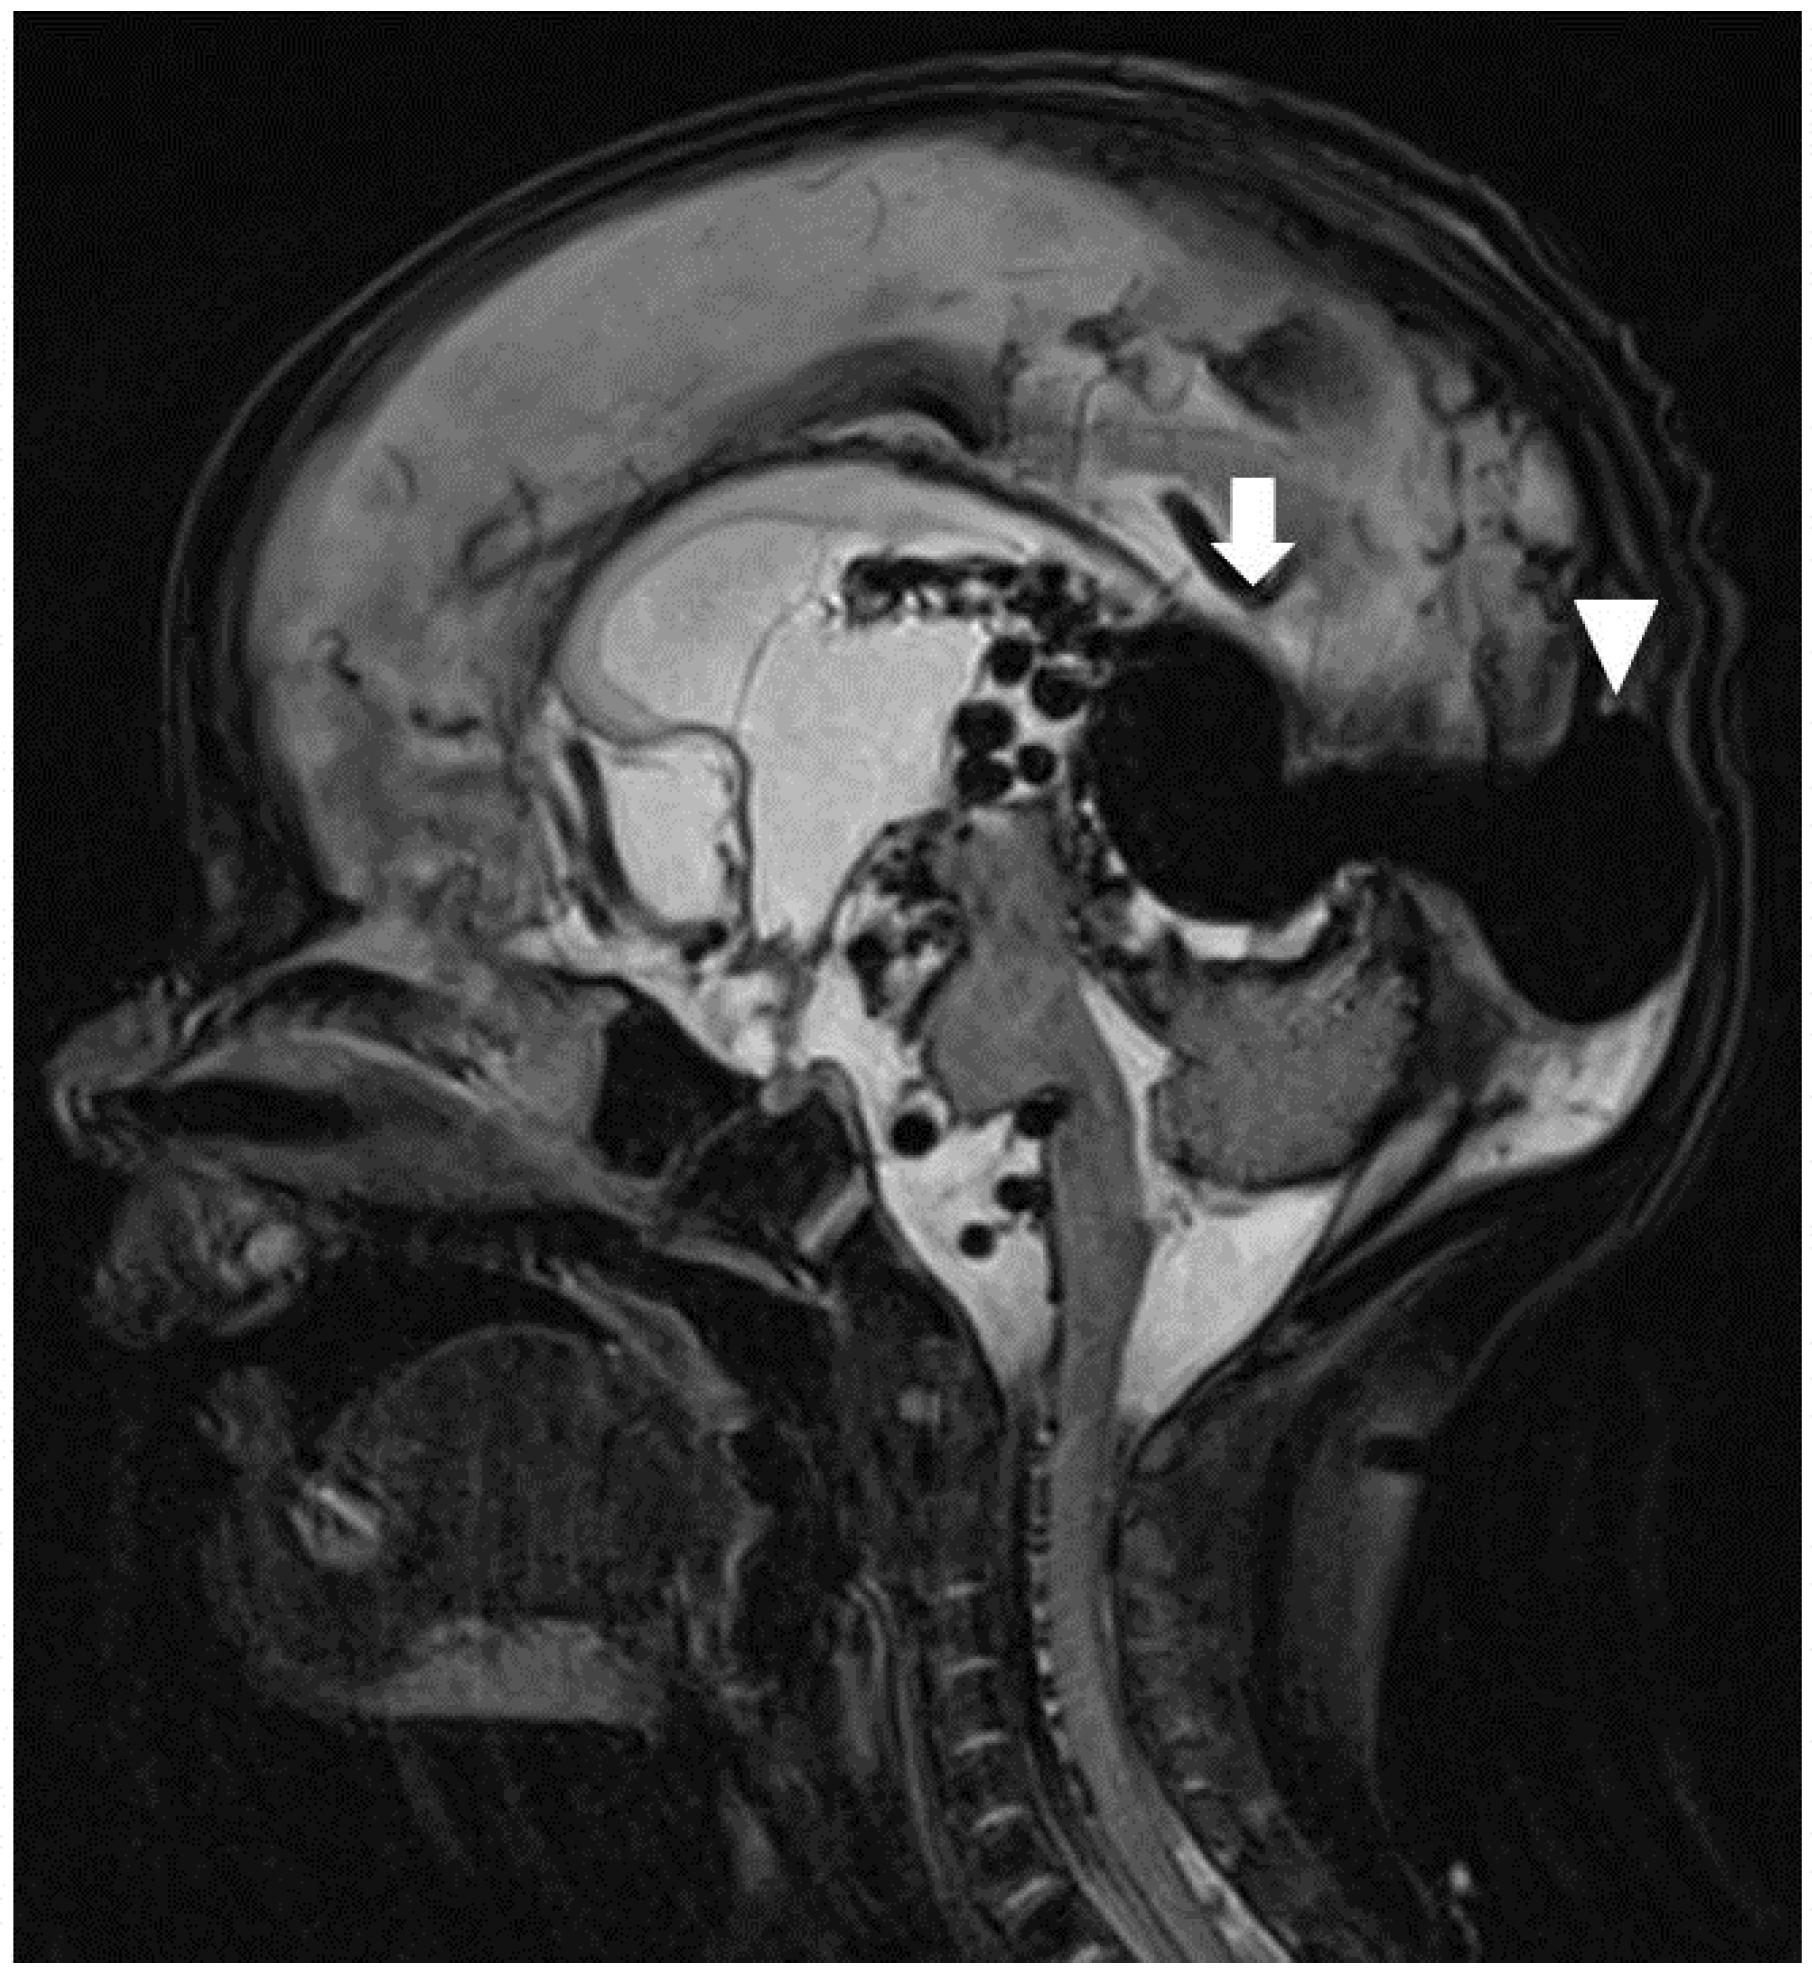

Full blood count, electrolytes, and inflammatory markers were normal on admission. Capillary blood gas showed metabolic acidosis (pH 7.24, pCO2 40, HCO3− 16.1 mmol/L, base excess −10.3, lactate 3.4 mmol/L). Chest X-ray showed cardiomegaly with no focal collapse or consolidation (Figure 1). The echocardiogram was normal, apart from a 2.9 mm patent ductus arteriosus with bidirectional flow and mild suprasystemic pulmonary hypertension.

Figure 1.

Frontal chest radiograph taken on day 1 demonstrating cardiomegaly predominantly in left chambers (Panel A) and worsening cardiomegaly on day 6 (Panel B). R denotes right side and L, left side.

On day 5 of life, the patient deteriorated with severe respiratory distress, poor perfusion, minimal responsiveness, oliguria, and hyponatraemia (Na 117 mmol/L). Examination revealed worsening generalized oedema, ascites, and hepatomegaly. This was attributed to congestive heart failure. Chest X-ray showed worsening cardiomegaly. The patient was managed with intubation and ventilation, fluid restriction, frusemide, bicarbonate correction, and the addition of cefotaxime.